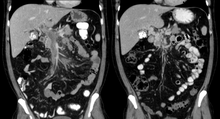

| Portal vein thrombosis seen with computed tomography. | |

The diagnosis of portal vein thrombosis is usually made by ultrasound, computed tomography with contrast or magnetic resonance imaging. D-dimer levels in the blood may be elevated as a result of fibrin degradation.